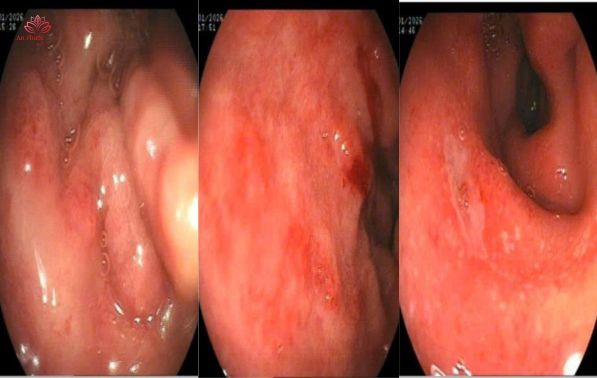

Nội soi tiêu hóa là phương pháp quan trọng nhất, cho phép quan sát trực tiếp niêm mạc dạ dày và tá tràng, đánh giá vị trí, kích thước ổ loét và lấy mẫu sinh thiết khi cần thiết.